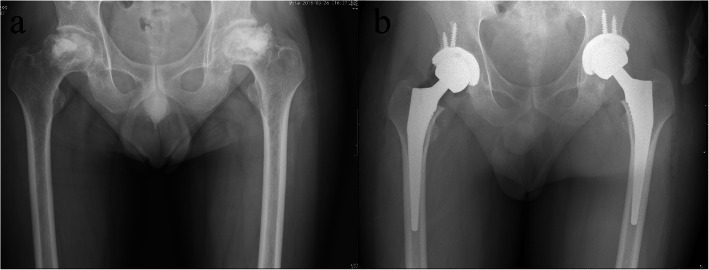

A 49-year-old male was referred to the orthopedic department of a tertiary hospital with pain in both hips for 19 months and the X-ray examination showed bilateral femoral head collapse and secondary osteoarthritis (ARCO stage IV osteonecrosis of the femoral head, ONFH) (Fig. 1a). He underwent craniocerebral surgery for craniopharyngioma approximately 2 years ago and had a long-term history of prednisolone administration (5 mg orally, twice daily for 2 yrs.). This patient received bilateral light bulb surgeries (removal of necrotic bone and impaction of artificial bone through a window at the femoral head-neck junction) 16 months ago and after that, hip pain was relieved for several months but aggravated 6 months ago. Considering his good physical condition, one-stage bilateral total hip arthroplasties were performed through a posterior approach. Two cementless press-fit endoprostheses were implanted on both sides using 52-mm PINNACLE cups with POROCOAT porous coating (Depuy, Warsaw, IN) and polyethylene liners with size 11 CORAIL stems (Depuy) with 36-mm ceramic heads (Fig. 1b).

Fig. 1.

The anteroposterior radiographs of bilateral hip joints before (a) and after (b) bilateral total hip arthroplasties. a Radiograph taken 2 days before THA showed bilateral femoral head collapse and secondary osteoarthritis, which indicated ARCO IV stage osteonecrosis of the femoral head; (b) radiograph taken immediately after bilateral THA showed satisfactory location and fixation of bilateral femoral and acetabular prostheses